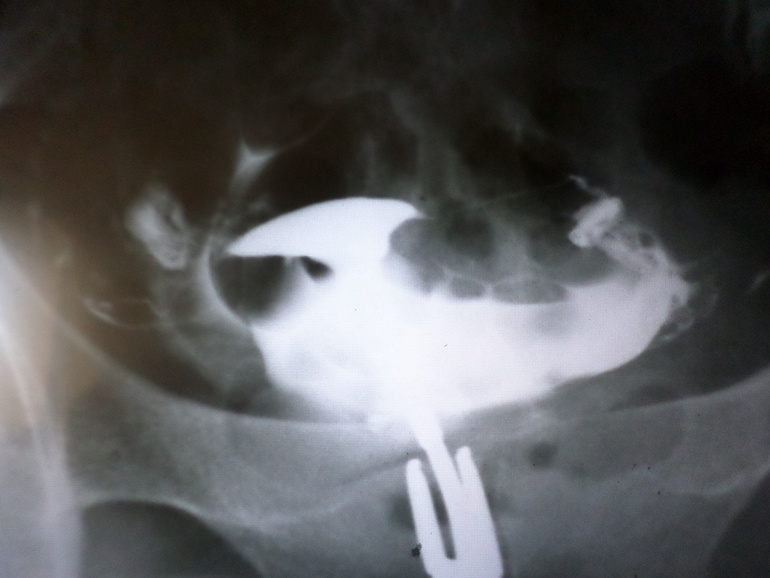

привет девчушечки. опять я здесь ) продолжается наше планирование, но пока впустую что то ((( отправила меня гиня на гсг, сделала, по результатам говорит все хорошо, теперь говорит больше исследовать нечего, все хорошо, старайтесь.... стараемся, а не выходит что то(( а тут еще снимок отдали а мне кажется там ничего не видно и все плохо. может у кого есть сравнить с моим? посмотрите пожалста))) я тут паникую...матка кажется кривая какая то(( трубы непонятные((

если смотреть по картинке левая труба (справа на картинке) прямая и отличная, она лучше всех проходима.

а вот правая труба (что слева на картинке) извилистая очень и контраста из нее меньше вышло.

))) все ок))) матка ( точнее ее полость) это треугольник сверху... Трубы отличные, прямые и ровненькие, все остальное - контраст в брюшной полости - это хорошо! Значит трубы проходимы